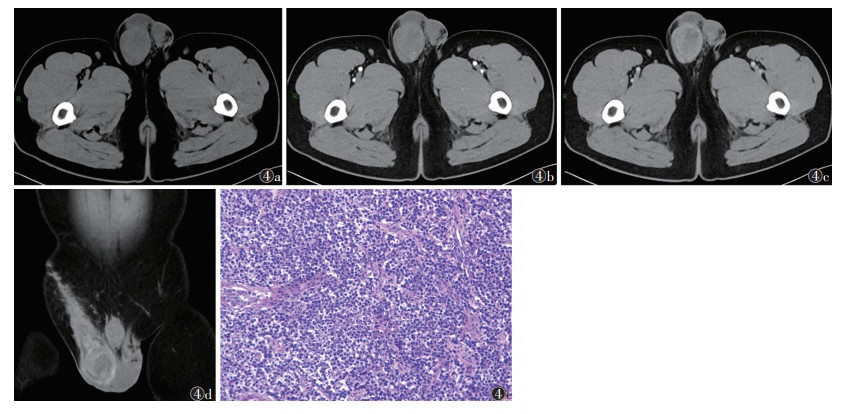

11例中,6例位于右侧睾丸,5例左侧。密度不均,CT值15~80 HU,肿瘤实性成分呈中度不均匀强化,边界清,囊性坏死区无强化,未见脂肪及钙化成分(图 4)。1例术后1个月复查发生远处转移。

| 注:患者,男,27岁。图 4a~4c分别为平扫、动脉期和静脉期图像;平扫图像示右侧睾丸体积轻度增大,见类圆形肿块,形态较规则,密度欠均匀,中心见片状液化坏死区;动脉期肿瘤实性成分呈中度不均匀强化,未见钙化及脂肪成分;静脉期肿瘤内供血血管强化程度减退。图 4d为冠状位重建图像,可见明显鞘膜积液。图 4e为病理图像,示肿瘤包含2种不同的类型的生殖细胞肿瘤成分,绝大多数为胚胎性癌(约占90%),少数为精原细胞瘤(约占10%)(HE染色,高倍放大) 图 4 睾丸混合性生殖细胞肿瘤CT图像和病理图像 |

混合性生殖细胞肿瘤于肿块内见多种肿瘤成分共存,其影像学表现与肿块内所含成分及所占比例有关。本组11例中,6例为精原细胞瘤与胚胎性癌不同比例混合,CT增强扫描肿瘤实性成分中度不均匀强化,囊性坏死区无强化,肿块内未见脂肪及钙化成分,其影像学表现介于精原细胞瘤与胚胎性癌之间。3例以精原细胞瘤为主、与其他生殖细胞肿瘤混合,其影像表现与精原细胞瘤类似。2例多种肿瘤共存的混合性生殖细胞肿瘤影像表现不典型,诊断较困难。